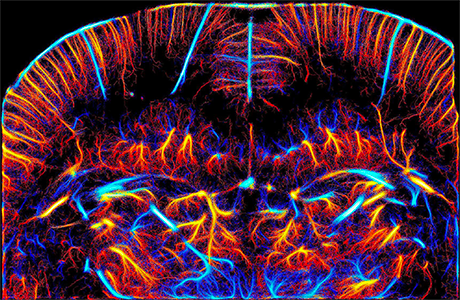

Imagerie super-résolution du réseau vasculaire d'un cerveau de rat, obtenue in vivo par microscopie ultrasonore, Couture et al., IEEE Transactions on Ultrasonics 2018

- L’imagerie super-résolution ultrasonore à l’échelle microscopique des vaisseaux capillaires des organes humains, marqueurs uniques du développement du cancer, des pathologies vasculaires ou neurologiques.